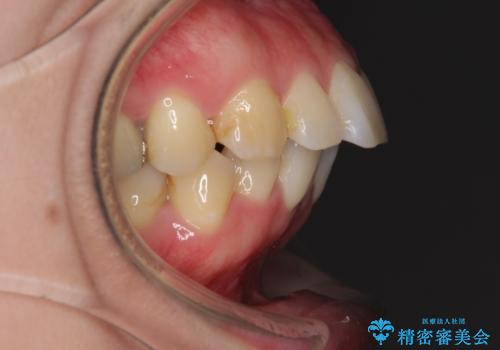

- 口が閉じずらく、口元が突出している状態でした。

上下左右の歯を1本ずつ、合計4本抜歯して、ワイヤーにて矯正することとなりました。

もともと下の前歯の永久歯が1本欠損しており、抜歯部位の選択を考慮しなければならない症例でした。シミュレーションを事前に行い、下顎の抜歯部位を決定しました。